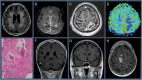

Figures